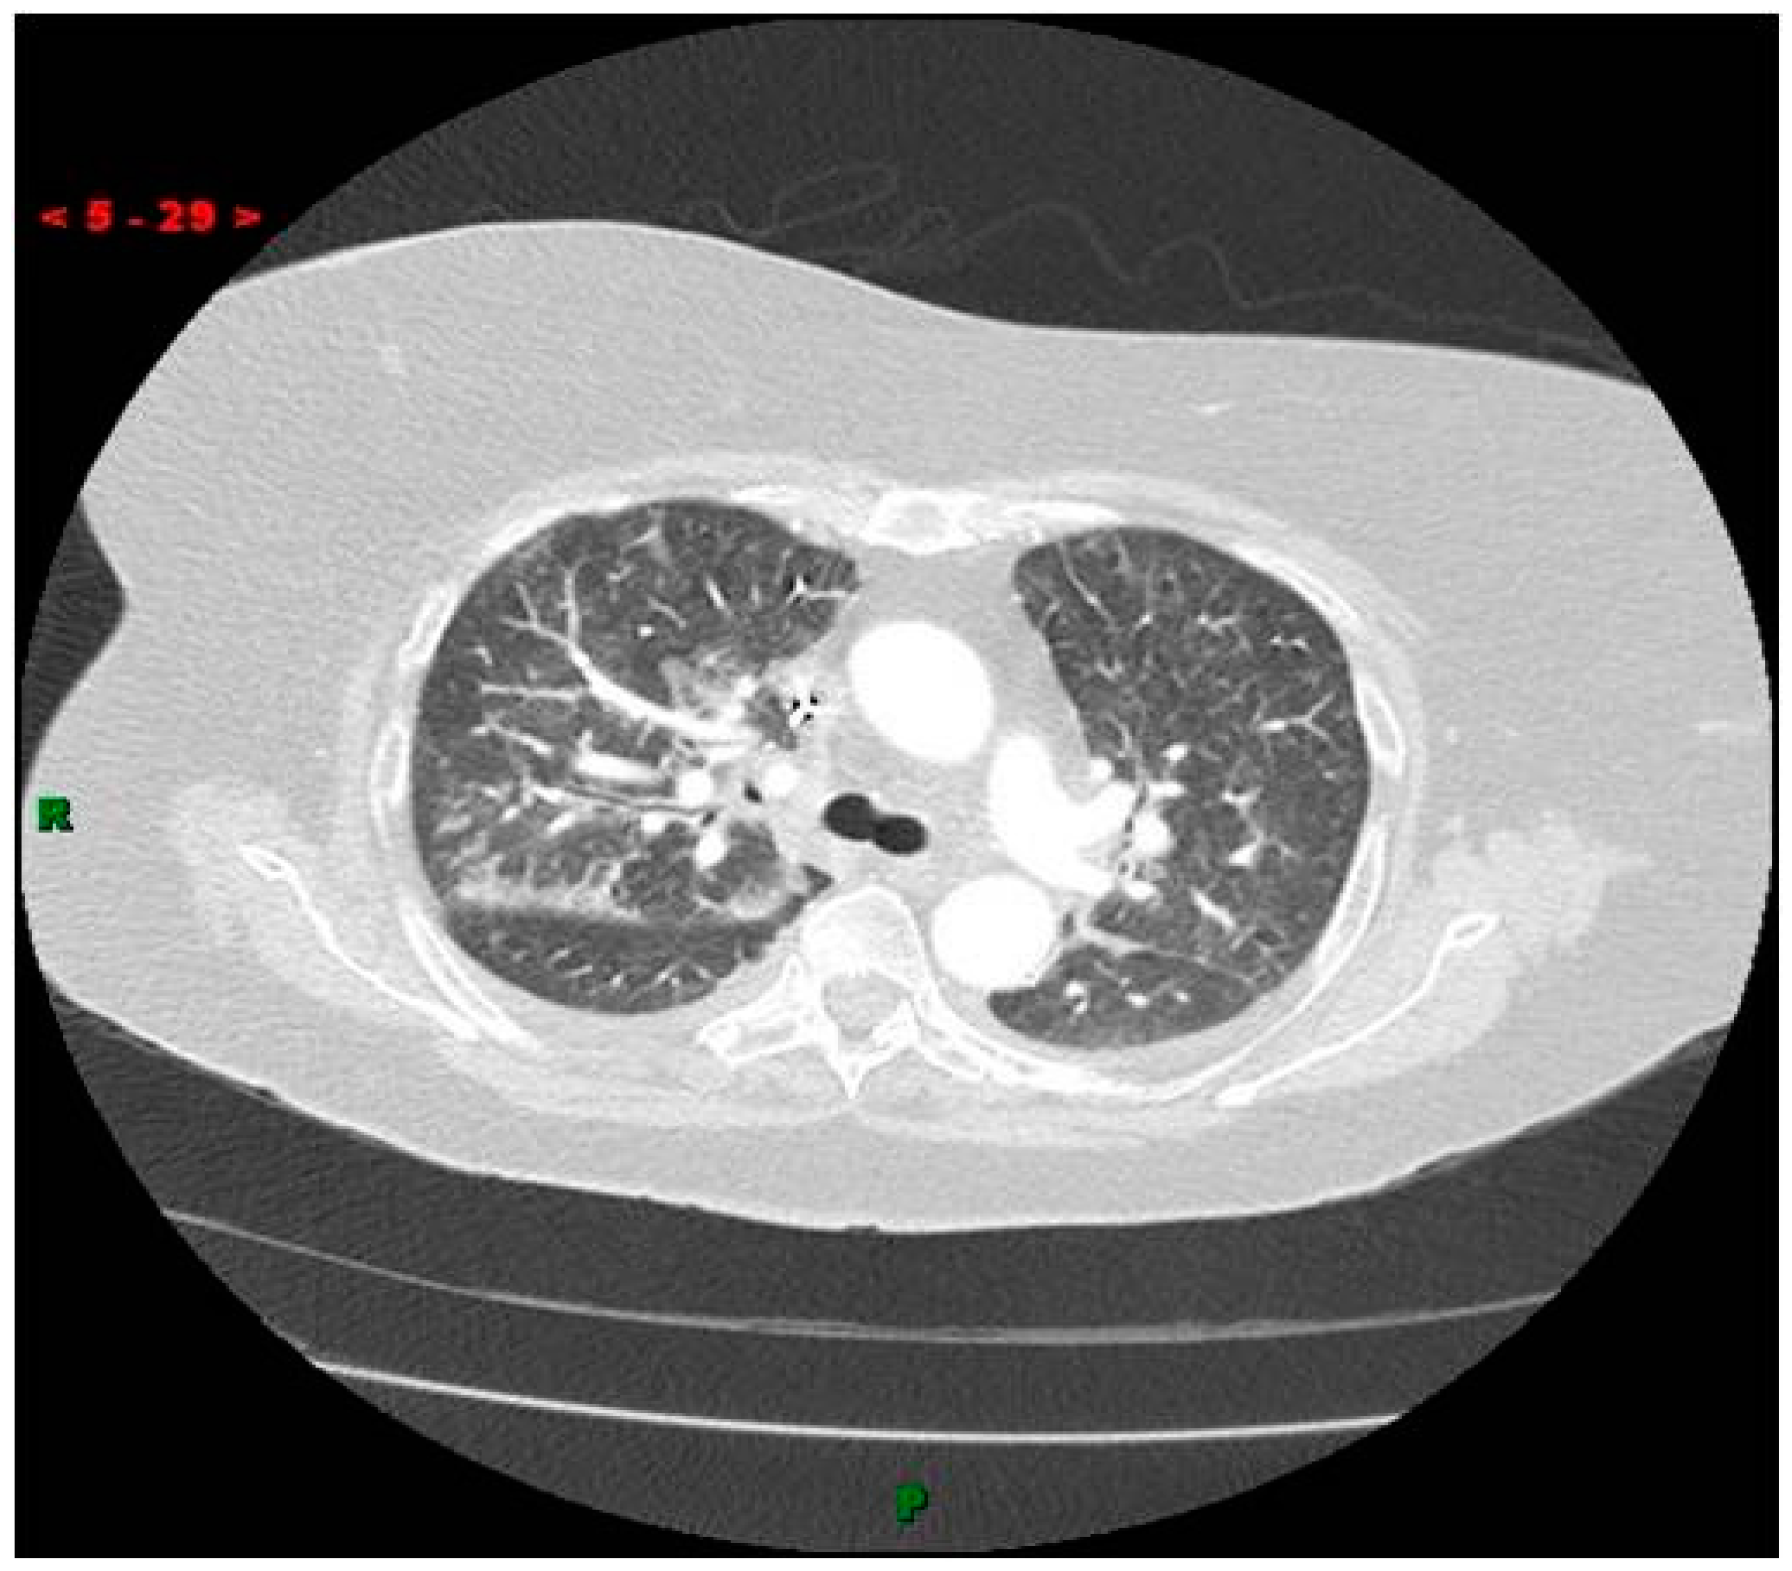

2.4. Intra-Cardiac Embolism Leading to Cardiovascular Deterioration

- Choe, D.H.; Marom, E.M.; Ahrar, K.; Truong, M.T.; Madewell, J.E. Pulmonary embolism of polymethyl methacrylate during percutaneous vertebroplasty and kyphoplasty. Am. J. Roentgenol. 2004, 183, 1097–1102. [Google Scholar] [CrossRef] [PubMed]

- Duran, C.; Sirvanci, M.; Aydoğan, M.; Ozturk, E.; Ozturk, C.; Akman, C. Pulmonary cement embolism: A complication of percutaneous vertebroplasty. Acta Radiol. 2007, 48, 854–859. [Google Scholar] [CrossRef] [PubMed]

- Krueger, A.; Bliemel, C.; Zettl, R.; Ruchholtz, S. Management of pulmonary cement embolism after percutaneous vertebroplasty and kyphoplasty: A systematic review of the literature. Eur. Spine J. 2009, 18, 1257–1265. [Google Scholar] [CrossRef] [PubMed]